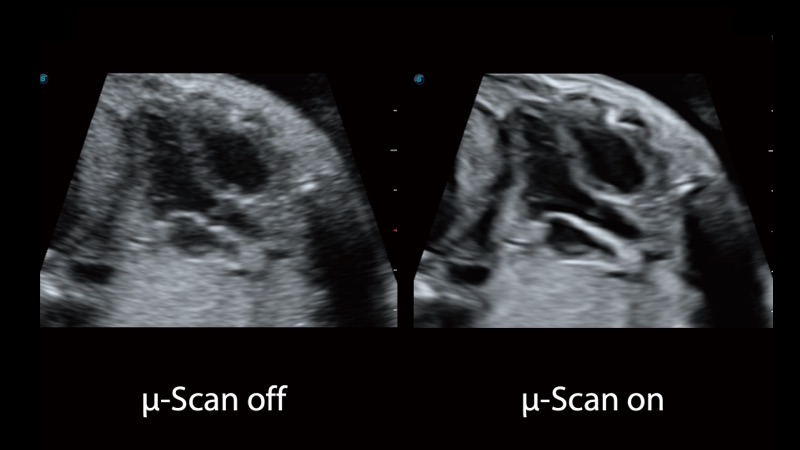

開立醫(yī)療通過不斷的技術(shù)創(chuàng)新,為大眾的生命健康提供持續(xù)關(guān)愛。P12 Plus采用全新一代超聲成像平臺(tái),新平臺(tái)旨在將真實(shí)還原組織解剖結(jié)構(gòu)作為首要目標(biāo)。平臺(tái)采用全新集成化硬件模塊,搭載新一代芯片,系統(tǒng)性能得到大幅提升,為您的診斷提供了豐富的臨床信息。優(yōu)異的圖像表現(xiàn),豐富的探頭配置,全面的應(yīng)用功能,為您日常診斷提供了可靠的助手。

彩色多普勒超聲診斷系統(tǒng)